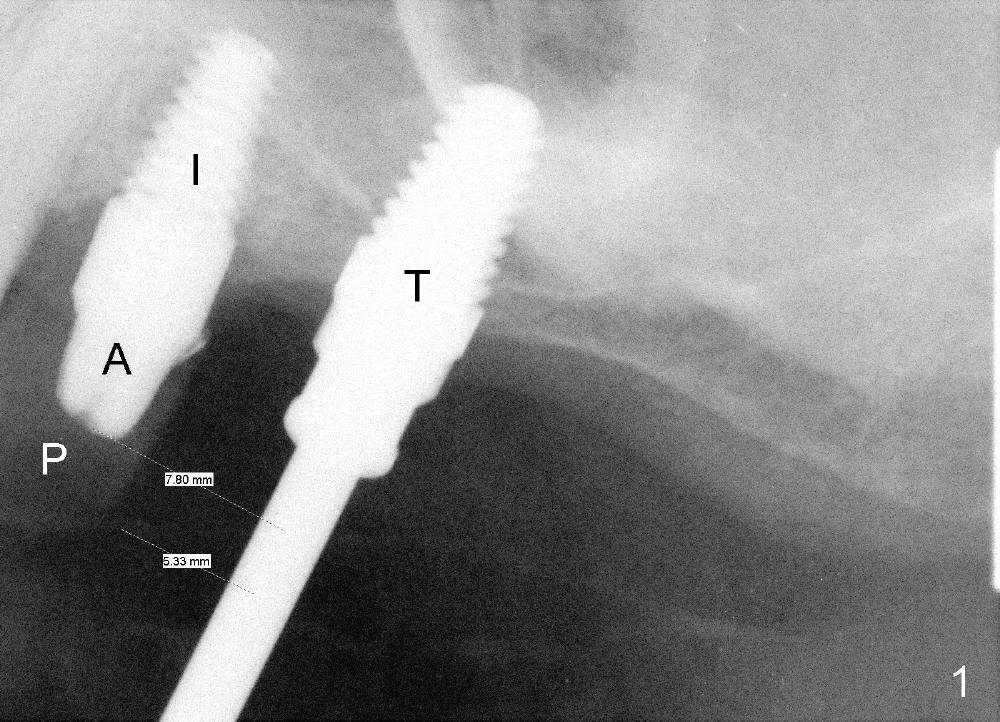

A lateral sinus window is created with a round diamond bur in high speed handpiece with copious irrigation as planned (Fig.3 W). The sinus membrane is lifted without tear. With the membrane protected with 2x2 gauze, an osteotomy (Fig.3 <) is developed at the site of the tooth #14 with 2 mm pilot drill, 2.5-3.5 mm reamers, 5x11 mm tap (Fig.1: T) and 6x11 mm tap. A synthetic bone graft (Osteogen 300-400 micron) is placed in the sinus before placement of 6x11 mm implant (Fig.4: 14). More of the synthetic bone mixed with autogenous bone is added superficial to the apex of the implant inside the sinus. The flaps are sutured.

The position and trajectory of the osteotomy (Fig.1 T) and subsequently those of the implant (Fig.4: 14) are aided by a surgical stent, which is fabricated from the model (Fig.2).